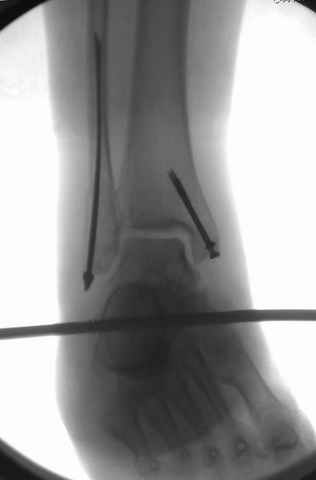

На прямой проекции послеоперационного Рг макроскопически все выглядит очень анатомично, при микроскопическом ( :-)) ) рассмотрении можно все-таки заметить вальгизацию тарана, суставная щель в латеральном отделе сустава несколько уже , чем в медиальном при отсутствии латерального смещения тарана. У меня был аналогичный случай (без LISS , без мини доступа) с вальгусным наклоном тарана при восстановленном ankle mortise при последовательном наблюдении с интервалами в 6-8 недель в послеоперационном периоде отмечалось прогрессирующее сужение суставной щели в латеральном отделе сустава, закончившееся посттравматическим ОА, к счастью боли умеренные, купируемые аналгетиками или своими эндорфинами:-))(активная пациентка, у которой нет времени на болезни....) Какова жизненная ситуация в приведенном вами случае? И последнее, что я хотел бы прояснить для себя - фиксация внутренней лодыжки: я обычно комбинирую фиксацию компрессирующим винтом со спицей - по идее ротационная стабильность должна быть лучше, чем один винт, каковы ваши наблюдения в этом плане?

Fixator, из минимальных доступов комбинированный метод для восстановления суставной поверхности-фиксация каннулированными

шурупами, создания жесткой системы фиксации до сращения перелома, защита от вальгусной деформации и на место образовавщегося метафизарного дефекта- костная пластика ауто костью или его

Дистракция в аппарате или на вытяжение результат - лигаментотаксис, посмотреть бы, как сегодня расположены отломки.